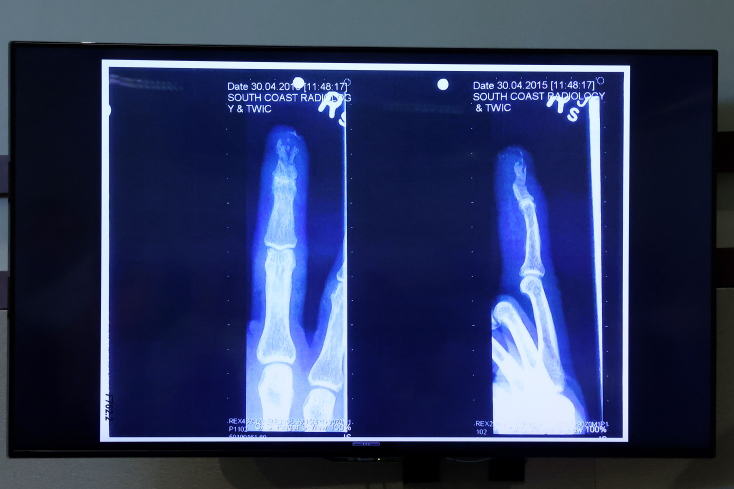

Ένα από τα σημαντικά στοιχεία που καθόρισαν τη δίκη ήταν όσα έγιναν το 2015 σε ένα ταξίδι του ζευγαριού στην Αυστραλία. Εκεί ο ηθοποιός γύριζε ταινία. Μετά από έναν καυγά κατά τη διάρκεια του ταξιδιού, ο Ντεπ υποστήριξε ότι τραυματίστηκε σοβαρά στο χέρι, όταν η Χερντ πέταξε ένα μπουκάλι βότκας που έσπασε. Ο ηθοποιός υποστήριξε ότι βρισκόταν σε κατάσταση σοκ όταν έγραψε συνθήματα στον τοίχο με το αίμα του.

Από την πλευρά της, η Άμπερ Χερντ αρνήθηκε ότι τον τραυμάτισε και ισχυρίστηκε ότι ο Τζόνι Ντεπ ήταν εκείνος που της επιτέθηκε σεξουαλικά. Χειρούργος από την ομάδα της Χερντ αποδόμησε τον Τζόνι Ντεπ υποστηρίζοντας ότι αν ο τραυματισμός του στο δάχτυλο ήταν τόσο σοβαρός, όσο περιέγραψε, θα είχε χάσει το νύχι του, κάτι που δεν συνέβη.

Ακτινογραφία με το χέρι του Τζόνι Ντεπ για τον φερόμενο ως τραυματισμό του από την Άμπερ Χερντ

Ακτινογραφία του Τζόνι Ντεπ © EPA